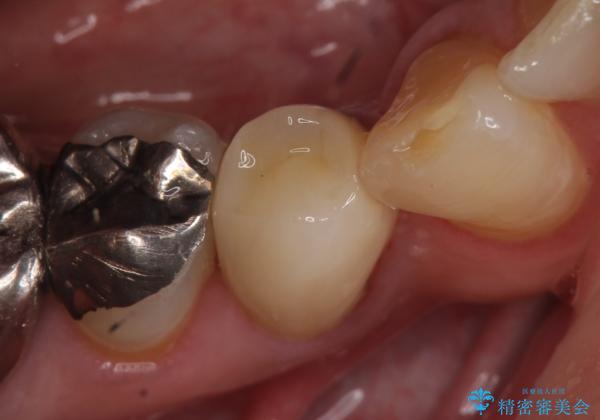

オールセラミッククラウン 再根管治療後の補綴

- 他院にて右下4番目の歯の再根管治療が必要だと言われた方の症例です。

再根管治療終了後、オールセラミッククラウンによる補綴を行いました。

今回用いたオールセラミッククラウンは、ジルコニアフレームという白い素材の上にセラミックを盛っているため審美性が非常に高いのが特徴です。

またジルコニアは人工ダイヤモンドの材料にも使われているほど高い強度を持っており、そのためオールセラミッククラウンは審美性だけでなく、奥歯やブリッジの補綴も可能とするクラウンです。